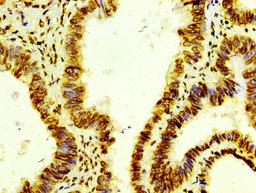

IHC image of CSB-RA010429A0HU diluted at 1:100 and staining in paraffin-embedded human colon cancer performed on a Leica BondTM system. After dewaxing and hydration, antigen retrieval was mediated by high pressure in a citrate buffer (pH 6.0). Section was blocked with 10% normal goat serum 30min at RT. Then primary antibody (1% BSA) was incubated at 4℃ overnight. The primary is detected by a biotinylated secondary antibody and visualized using an HRP conjugated SP system.